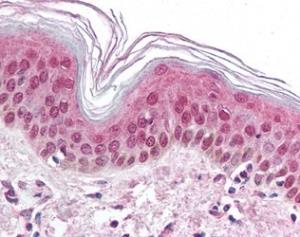

Auga virsējās kārtas šūna (mikrofotogrāfija)

Cilvēka ādu veido segaudi

Augu virsmu klāj segaudi